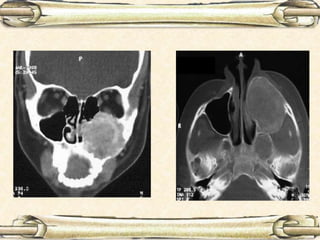

C.T. Scan Nose & Paranasal sinus: expansion & destruction of bony wall

C.T. Scan

Diagnostic nasal endoscopy C.T.Scan Nose & Paranasal sinus: expansion & destruction of bony wall Biopsy Diagnosis